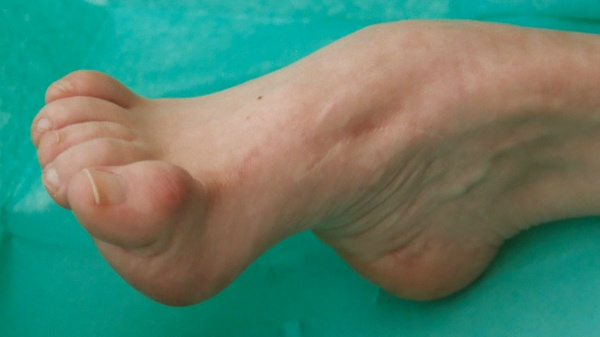

Наблюдается эквинус, варусная деформация (стопа подогнута, пальцы отклонены кнутри) и супинация (стопа развернута подошвой кверху и кнутри). Движения в голеностопном суставе ограничены. Из-за изменения положения стопы ребенок с косолапостью при ходьбе опирается не на всю подошву, а на наружный край стопы. Развивается своеобразная походка, при которой больной во время каждого шага перешагивает через опорную ногу.

(Справа) Клиническая фотография того же пациента вскоре после УЗИ. Расщепление позвоночника и косолапость повторяют находки при УЗИ в 20 нед. (Слева) УЗИ плода с дистальным артро-грипозом. Запястья в стойком согнутом положении, пястно-фаланговые суставы и кисти рук разогнуты. Кроме того, определяются двусторонняя косолапость и выраженная атрофия мышц нижних конечностей (по сравнению с подкожной жировой клетчаткой).

(Справа) Тот же случай. Клиническая фотография новорожденного. Ультразвуковые находки подтверждены. При выявлении двусторонней косолапости необходимо внимательно исследовать верхние конечности. (Слева) УЗИ плода во II триместре. Синдром множественных птеригиумов и водянка плода (не показана). Фиксированные контрактуры кистей, кожная складка в области локтевого сустава и выраженная косолапость.